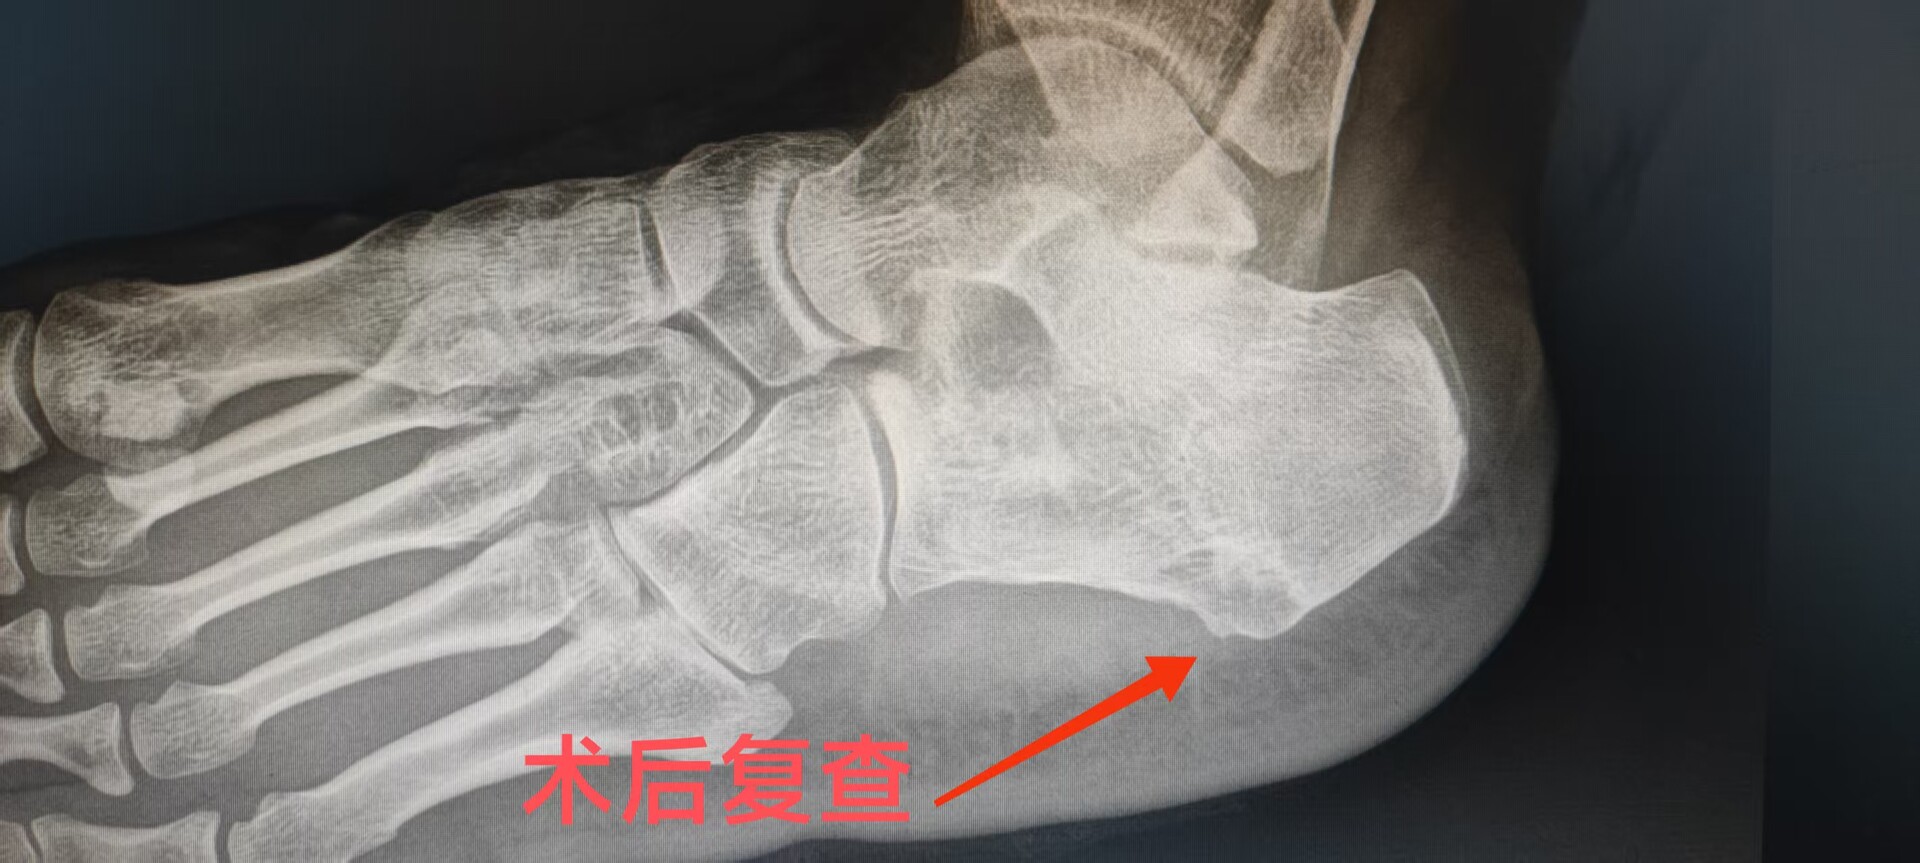

患者李女士被左足跟疼痛困扰了5年多,尤其是晨起下床的第一步疼痛最为剧烈。她尝试过冲击波、封闭针和理疗,但症状反复,最近甚至开始跛行,生活质量大受影响。术前X光显示,她的跟骨结节处有明显的“鸟嘴状”骨刺。